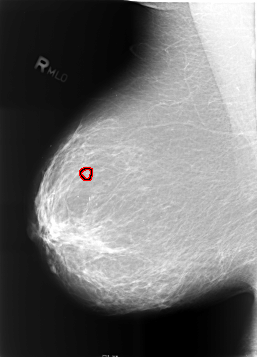

ics_version 1.0 filename B-3465-1 DATE_OF_STUDY 12 5 1998 PATIENT_AGE 67 FILM FILM_TYPE REGULAR DENSITY 2 DATE_DIGITIZED 7 4 1999 DIGITIZER LUMISYS LASER SEQUENCE LEFT_CC LINES 5680 PIXELS_PER_LINE 4176 BITS_PER_PIXEL 12 RESOLUTION 50 NON_OVERLAY LEFT_MLO LINES 5704 PIXELS_PER_LINE 4152 BITS_PER_PIXEL 12 RESOLUTION 50 NON_OVERLAY RIGHT_CC LINES 5696 PIXELS_PER_LINE 4088 BITS_PER_PIXEL 12 RESOLUTION 50 OVERLAY RIGHT_MLO LINES 5712 PIXELS_PER_LINE 4104 BITS_PER_PIXEL 12 RESOLUTION 50 OVERLAY |

FILE: B_3465_1.RIGHT_MLO.OVERLAY TOTAL_ABNORMALITIES 1 ABNORMALITY 1 LESION_TYPE CALCIFICATION TYPE AMORPHOUS-PLEOMORPHIC DISTRIBUTION CLUSTERED ASSESSMENT 4 SUBTLETY 2 PATHOLOGY BENIGN TOTAL_OUTLINES 1 BOUNDARY |

FILE: B_3465_1.RIGHT_CC.OVERLAY TOTAL_ABNORMALITIES 1 ABNORMALITY 1 LESION_TYPE CALCIFICATION TYPE PLEOMORPHIC DISTRIBUTION CLUSTERED ASSESSMENT 4 SUBTLETY 2 PATHOLOGY BENIGN TOTAL_OUTLINES 1 BOUNDARY |